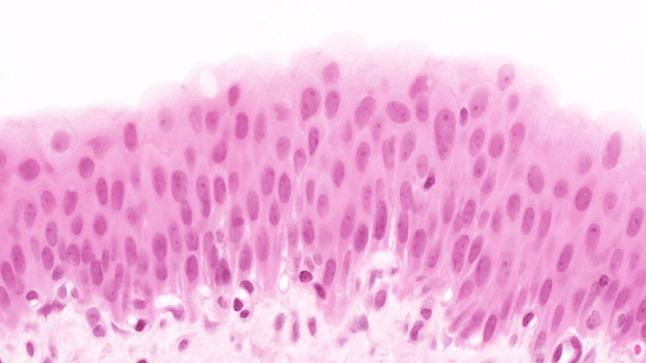

The morphology of experimentally induced urinary bladder precancerous lesions has been differentially interpreted in the literature. Here, we aimed to describe the development of precancerous lesions of the urothelium histologically and by DNA cytophotometric analysis.

We induced precancerous lesions of the urothelium in 60 Wistar rats with 0.05 % N-butyl-N-(4-hydroxybutyl)nitrosamine (BBN) solution as drinking water. After exposure for 2-20 weeks, each animal received tap water for 2 weeks. Subsequently, six animals were killed every 2 weeks, and urothelia of three urinary bladders per time point were examined by DNA cytophotometry of smear preparations. An additional three urinary bladders were processed for histological analysis.

Over 20 weeks, BBN exposure led to a significant difference between the control group and most of the BBN-exposed 2-week groups and to differences between most of these time point groups. After week 4, this difference included a higher proportion of cells with increased nuclear DNA content. At the end of the experiment, DNA cytophotometric values of the urothelium in experimental rats corresponded to those of poorly differentiated urothelial carcinomas.

Biologically significant stages of precancerous lesions were already detectable after 4 weeks of BBN exposure, considerably earlier than previously described in the literature.